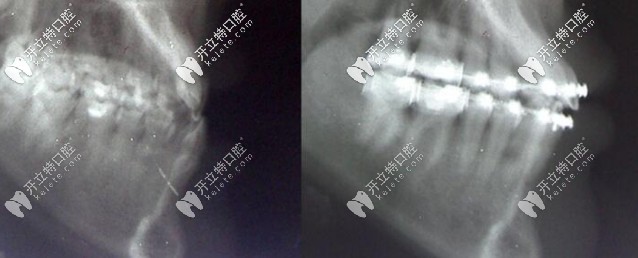

用帶狀弓矯正器矯正骨性Ⅲ類錯合矯治前后